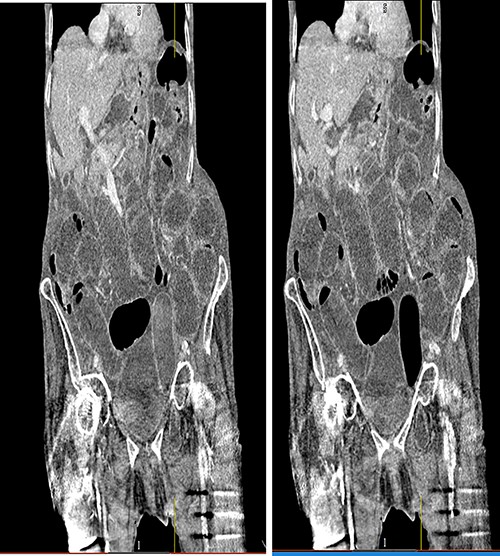

Following surgical review, a computerized tomography (CT) scan of the abdomen and pelvis was requested and showed small bowel obstruction, secondary to a left-sided obturator hernia (Figs 1 and 2).

Coronal view CT scan with IV contrast showing dilated small bowel loops and bowel loop through the left obturator canal.